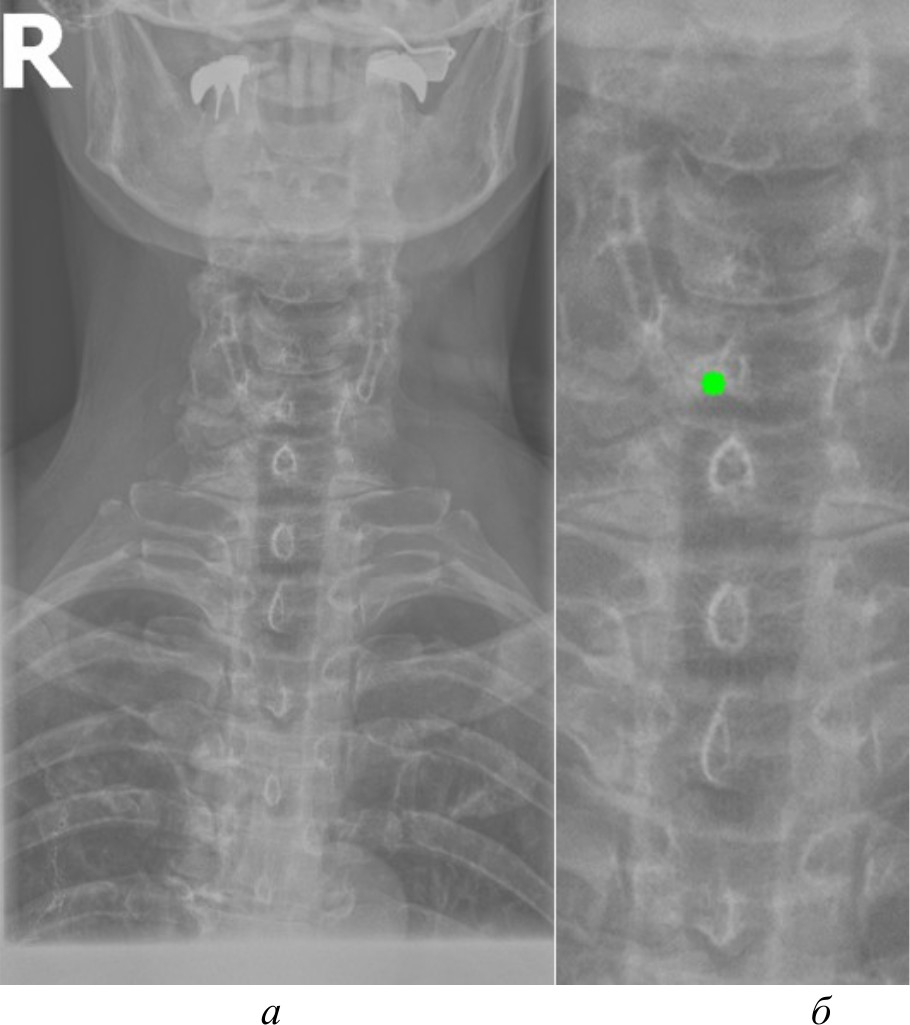

На рис. 9 представлены результаты работы системы поддержки принятия врачебных решений.

Рис. 9. Результаты работы системы поддержки принятия врачебных решений

Система включает в себя следующие ключевые возможности:

- автоматическая предварительная обработка медицинских изображений. Система использует метод стандартной эквализации, который показал наилучшие результаты по точности распознавания анатомических ориентиров;

- кластеризация и распознавание анатомических ориентиров. Алгоритм Shi-Tomasi применяется для выделения ключевых элементов позвоночника на изображениях, сгруппированных в 5–6 кластеров. Точность распознавания достигает 95 %;

- интеллектуальная система поддержки диагностики. На основе выделенных анатомических ориентиров система может предложить врачу предварительные диагнозы, а также рекомендации по дальнейшему обследованию пациента.

Таким образом, данная система упрощает процессы диагностики заболеваний позвоночника, а также облегчает работу медицинского персонала.